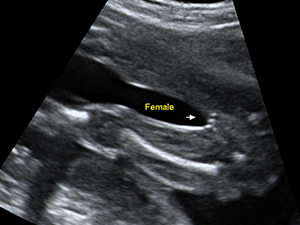

Gender - Female

Female genital organ (arrow) at 20 weeks